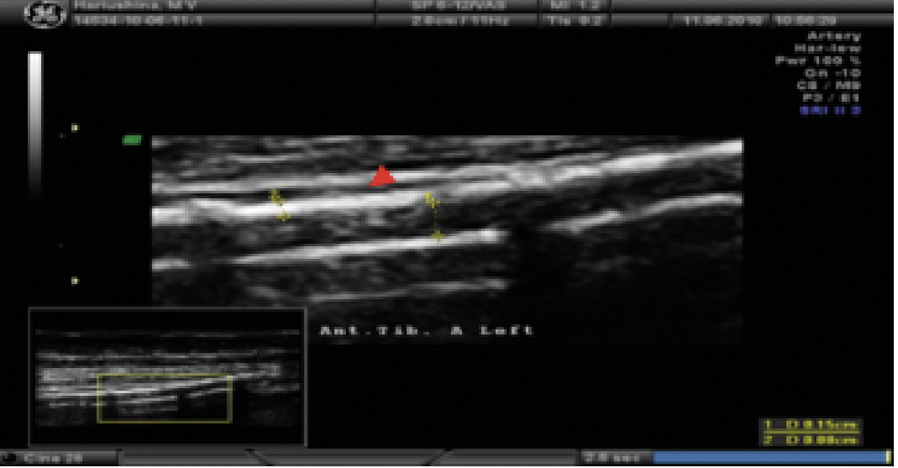

При ультразвуковом дуплексном сканировании артерий нижних конечностей в 2022 г. выявлен атеросклероз магистральных артерий нижних конечностей, эхографические признаки выраженного кальциноза магистральных артерий (рис. 4), окклюзирующий хронический тромбоз левой задней большеберцовой артерии в верхней и средней трети голени.

Рис. 4. Эхограмма пациента Т. Левая передняя большеберцовая артерия. Визуализируется диффузное относительно равномерное повышение эхогенности сосудистой стенки в сочетании с утратой дифференцировки на слои на всем протяжении (красная стрелка). Эхографические тени от повышенного содержания солей кальция фрагментарно перекрывают просвет и нижнюю стенку сосуда (желтые стрелки)

При измерении лодыжечно-плечевого индекса (ЛПИ) доплеровский сигнал не исчезал даже в случае нагнетания давления в манжете более 300 мм рт. ст. по трем измеряемым артериям. По левой окклюзированной в проксимальном сегменте задней большеберцовой артерии получен показатель 1,3, что отражает значимую кальцификацию сосудистой стенки. Распространение кальциноза наблюдалось и на пальцевые артерии, что сопровождалось несжимаемостью этих артерий, свойственной пациентам с ХБП, получающим заместительную почечную терапию, или пациентам после трансплантации почки. По данным ультразвукового дуплексного сканирования внечерепных отделов брахиоцефальных артерий, в устье левой внутренней сонной артерии выявлена кальцинированная атеросклеротическая бляшка (стеноз 20%). Ультразвуковое дуплексное сканирование артериовенозной фистулы левой верхней конечности: эхографические признаки кальциноза (рис. 5) с симптомами ускоренного кровотока в бассейне левой плечевой артерии (230 см/с) в сравнении с контрлатеральной плечевой артерией (77 см/с). Избыточное шунтирование артериальной крови по фистуле напрямую в венозное русло, предположительно, может способствовать развитию ригидности сосудистой стенки, что обусловлено изменением кинетических характеристик движущейся крови (давления, объема, скорости), иными словами, «напряжением сдвига». Вследствие повышенного воздействия на механорецепторы эндотелия могут активироваться патологические процессы, направленные на активацию сосудистой кальцификации у нашего пациента.